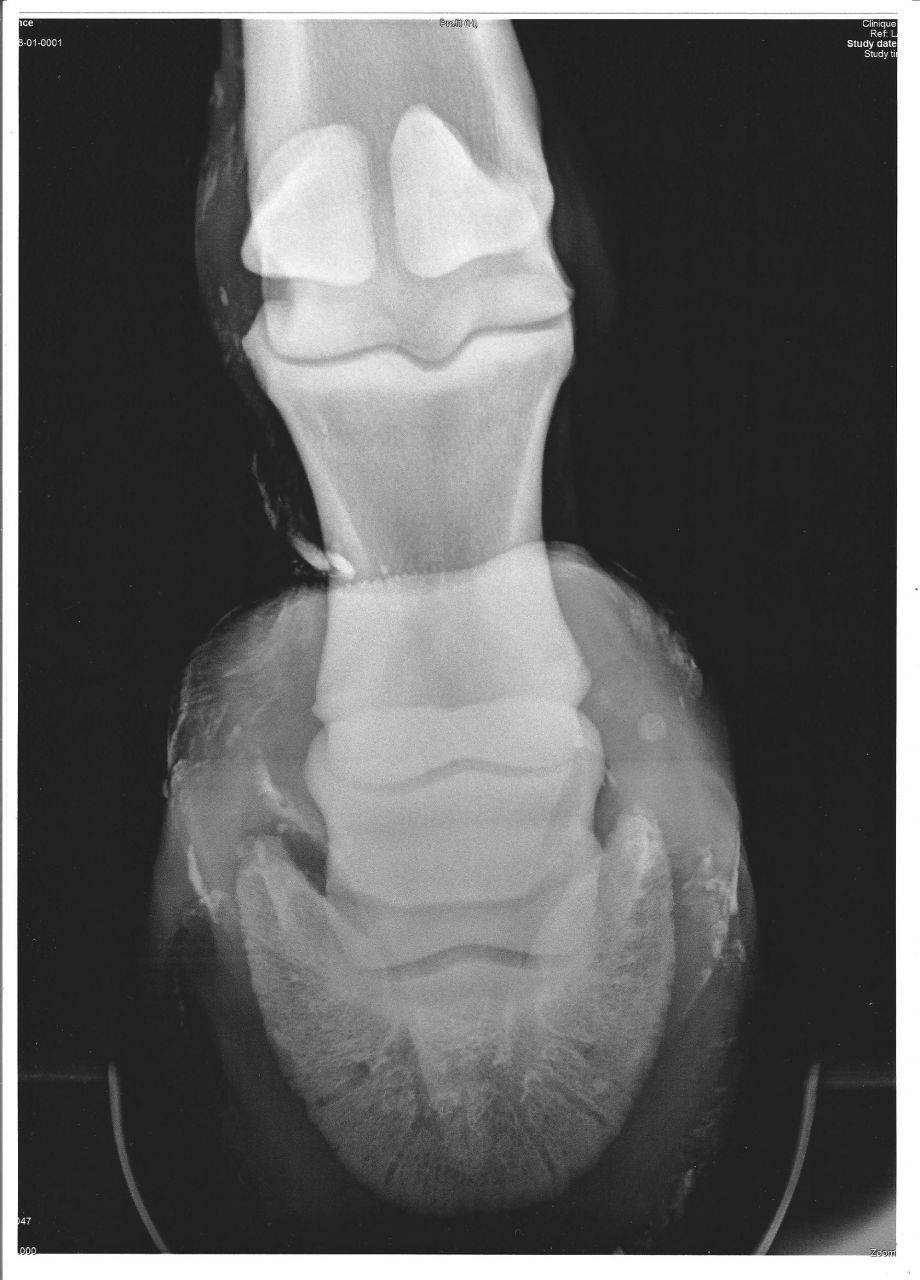

| Dire merci | Tout est dis dans le titre... Fracture du processus palmaire sur un Fijord de 9 ans, non ferré... Mais sa boiterie ne viendai pas de là, il ne réagit pas au test avec la pince... ( boiterie, sans doute, antérieure à la fracture d'après mon véto ) En attendant que mon véto me donne les consignes à suivre, je vais le mettre en box et s'il ne supporte pas, je le mettrai en petit parc... Je pence aussi faire venir le maréchal ferrant ( ferrure ? ) Je pence que c'est le mieux à faire en attendant... Je ne vais pas faire une bêtise ? Merci d'avance pour vos avis Voici les radios : ( c'est juste au dessu du vice ) ![]() ![]() |

| Dire merci | t'as pas des obliques??? ![]() pour diagnostiquer une fracture de P3, il faut parfois faire beaucoup de radios, parce que si on n'est pas pile poil dans l'angle, on peut la louper. en l'occurrence, 2 obliques en skyline sont un grand minimum pour diagnostiquer une fracture de processus palmaire... meme si on la voit pas mal sur la radio de profil (et ça ne réagit pas forcément à la pince ) |

| Dire merci | al non, j'ai que çà... une fracture de P3, P3 c'est le processus palmaire ? C'est comment 2 obliques en skyline ? |

| Dire merci | P3 c'est la 3ème phalange, soit l'os qui est dans le pied ![]() pour le reste, je laisserai AL répondre ![]() le fer boîte, est un fer qui limite au max les mouvements du pied (boite cornée), ceci afin de moins solliciter les parties abimées lors de leur cicatrisation |